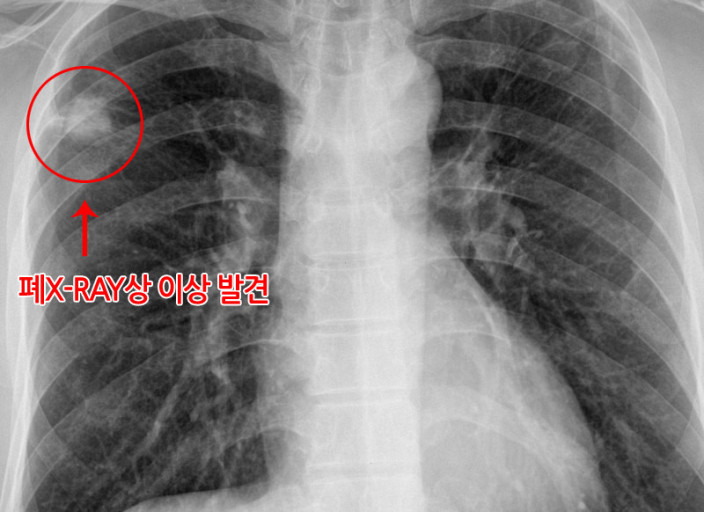

폐렴 증상 폐렴은 폐의 세균, 바이러스, 곰팡이 등 감염으로 인해

폐포(폐 속의 공기 주머니)에 염증이 생기고, 고름이나 액체가 차는 질환입니다.